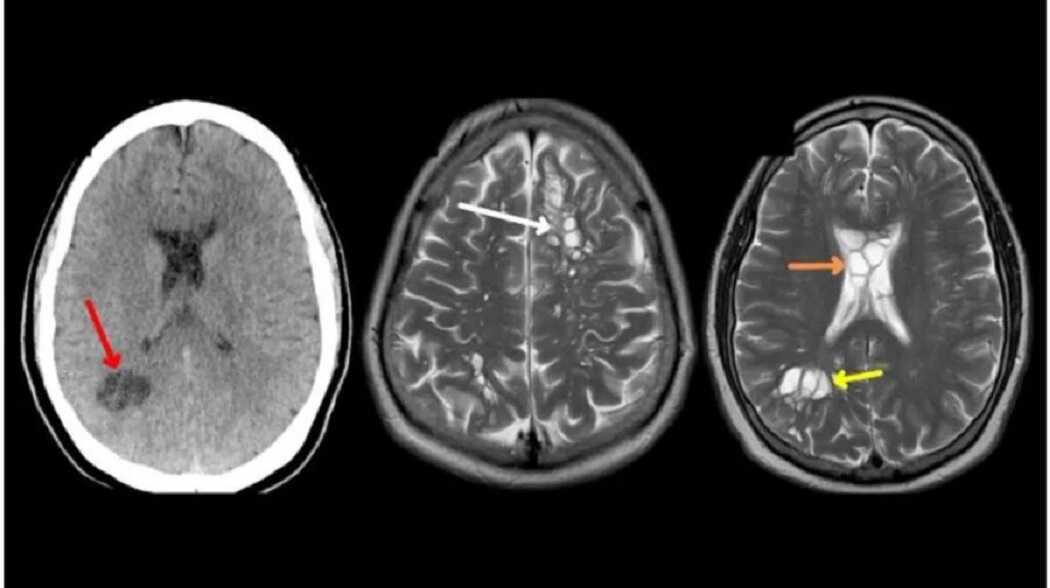

Un hombre de 52 años de Florida, Estados Unidos, comenzó a sufrir de intensos dolores de cabeza durante cuatro meses. Ante la preocupación que le generaba su estado de salud, decidió acudir a un médico para averiguar lo que le estaba sucediendo.

Según publicó un informe del American Journal of Case Reports, el hombre -cuya identidad no fue revelada- comenzó a sufrir de migrañas después de empezar a consumir el alimento con poca cocción. De esta manera, con el tiempo, desarrolló neurocisticercosis, una infección en donde un parásito deposita huevos en varias partes del cuerpo, particularmente en el cerebro.

Ante la consulta del paciente, su médico de cabecera lo sometió a una tomografía en donde se logró visualizar una gran cantidad de quistes en la cabeza.

La sospecha llegó cuando intentaron profundizar sobre el origen de la afección, ya que la neurocisticercosis es común entre las personas que viven en países con malas condiciones sanitarias o están en constantes contacto con cerdos, el animal de donde se contagia el parásito. Sin embargo, el hombre no cumplía con ninguno de estos factores de riesgo.

Finalmente, durante las consultas, el paciente confesó que, desde siempre, tuvo una forma particular de comer la panceta: “Lo hago poco cocido y no crujiente”, expresó. Por esta razón, los especialistas concluyeron que había contraído la infección en el cerebro a partir de una tenia intestinal.

“Sólo se puede especular, pero dada la predilección de nuestro paciente por la carne de cerdo poco cocinada y su historial de exposición benigna, somos partidarios de que su cisticercosis se transmitió por autoinfección tras un lavado de manos inadecuado, después de que él mismo hubiera contraído la teniasis por sus hábitos alimentarios”, explicó el informe.

Según los expertos, el hombre fue tratado con un medicamento parasitario y presentó mejoras significativas en cuestión de dos semanas.